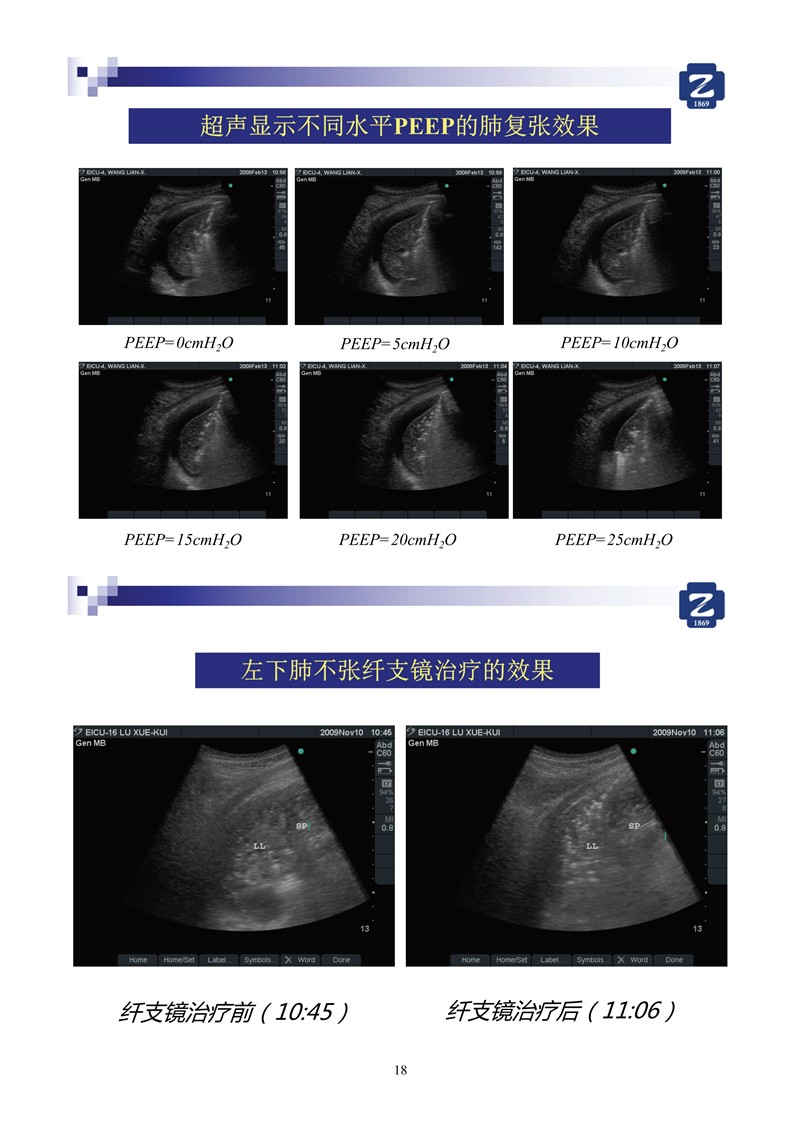

第二版新型冠狀病毒肺炎超聲診斷實用手冊_2.jpg